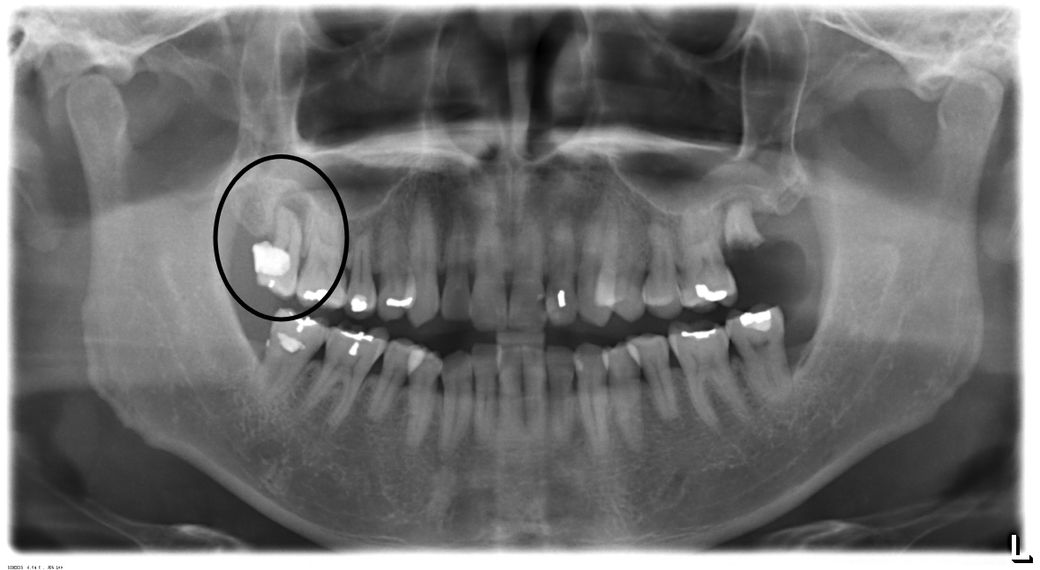

사진 속 원 안의 치아를 꼭 빼야 할까요?

왼쪽 어금니가 부러져 치과에 갔다가 오른쪽 어금니도 뽑아야 한다는 말을 들었습니다.

전혀 아프지도 아무런 증상도 없는데 꼭 뽑아야 하나요?

혹시 잇몸치료로는 안 될까요?

치아를 받치고 있는 잇몸뼈가 완전히 녹아있는 상태로 보이며 살릴 수 없다고 판단됩니다.

• 맞습니다. 해당 치아는 이미 뿌리까지 염증이 있어 다른 x-ray 사진을 찍지 않더라도 발치를 반드시 해야 하는 치아입니다. 계속해서 방치하면 광대뼈까지 염증이 나타날 가능성이 높습니다.

• 사진으로 봤을 경우에는 신경관 내부에 감염으로 인해서 뿌리 쪽에 큰 염증이 생긴 것으로 보입니다 치아가 아프거나 흔들림이 심하다면 발치를 해야 할 수 있습니다 뿌리 쪽에 생긴 염증은 신경관이 감염이 되어서 생겨서 가능성이 높기 때문에 신경치료를 시도해 본다면 치아를 살려서 사용할수도 있습니다 자세한 확인을 위해서 치과에서 진료를 받아 보는 것을 권유드립니다

• 안녕하세요 치과의사 김철진입니다. 치아 뿌리끝에 염증이 심한거 같습니다. 치아가 많이 흔들릴것같은데 발치를 하셔야될것같습니다.

• 사진상 치아의 경우 주변 뼈가 다 녹아서 치아 수직 동요도가 있을 정도 같습니다 이정도면 잇몸치료는 무의미할것 같습니다

다만 특별히 불편한점이 없다면 그냥 쓸때까지 쓰고 빼시면 되겠습니다